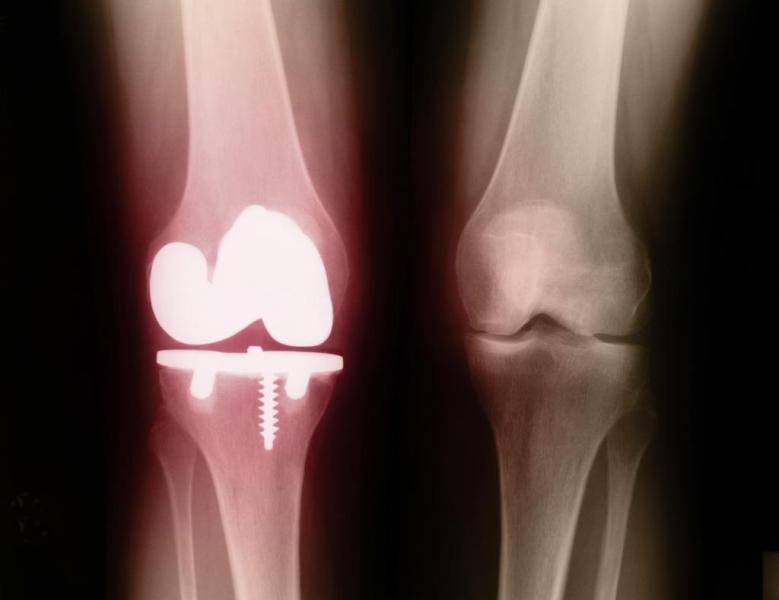

Для подтверждения диагноза назначается рентгенография. Рентгенологическими признаками псориатического артрита являются:

- Остеопороз костей, расположенных около воспаленного сустава;

- Уменьшение размера суставной щели;

- Кистовидные просветления;

- Костные узуры (эрозии);

- Анкилоз (сращение) костей и суставов;

- Параспинальные оссификации – обызвествление мягких тканей рядом с позвонками;

- Сакроилеит – воспаление, охватывающее крестцово-подвздошный сустав.

Рентгенологическое исследование сустава

Рентгенологические признаки суставного псориаза множественные костные разрастания в полость сустава. При псориатическом спондилоартрите между позвонками образуются костные разрастания и перемычки, а соединительная ткань хрящей превращается в костную.

При мутилирующей форме разрастания сопровождаются краевыми эрозиями, а то и полным разрушением головок костей, грубыми анкилозами, фиксирующими сустав постоянно в одном и том же положении и исключающими любые движения в нём.